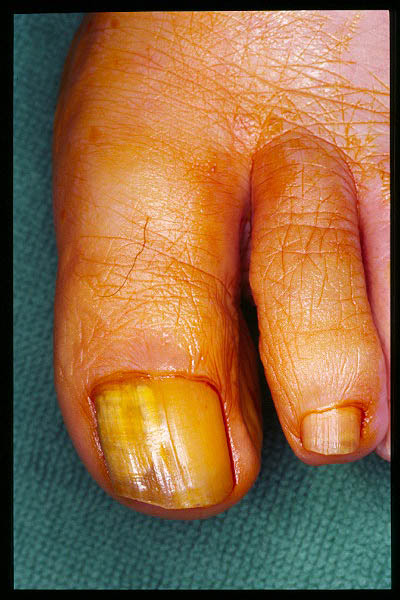

Uña estriada. Onicogrifosis.